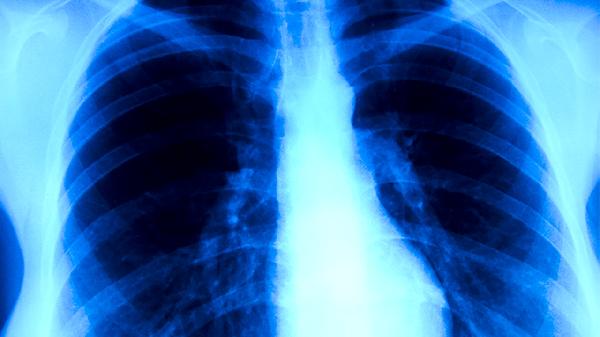

胸部X线检查可发现肺结核的典型表现如肺上叶浸润、空洞形成等。该检查能评估病变范围和严重程度,但无法直接确认病原体。不同时期的肺结核在X线下表现各异,需结合临床表现和其他检查结果进行诊断。